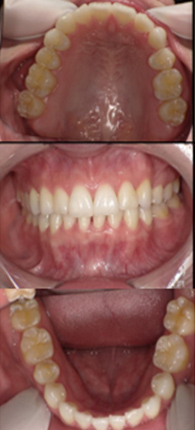

症例2

前歯の歯並びをきれいに整えたいとご来院された20代女性の症例です。18枚のインビザラインを用いて上下の歯列を拡大し、骨格に問題のないⅠ級叢生のケースに対応しました。

約10か月後

ホワイトニング併用

| 治療費用 | 矯正検査代 33,000円、基本治療費 660,000円、調整料 5,500円×10回、 保定装置 55,000円、ホワイトニング剤 6,600円 |

| 治療のリスクについて | ホワイトニングでは歯がしみることがありますが、当院では知覚過敏予防の歯磨剤をお渡しし、症状の軽減に努めています。また、矯正治療においては歯肉退縮のリスクがありますが、丁寧な歯磨き指導を行うことで予防に取り組んでいます。 |